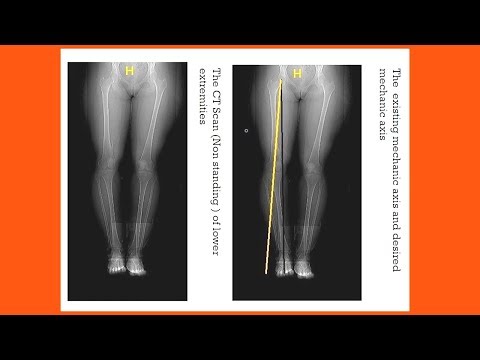

High Tibial Osteotomy ( Open Wedge Technique )

This video simply explains the logic and the technique of the open wedge high tibial osteotomy.